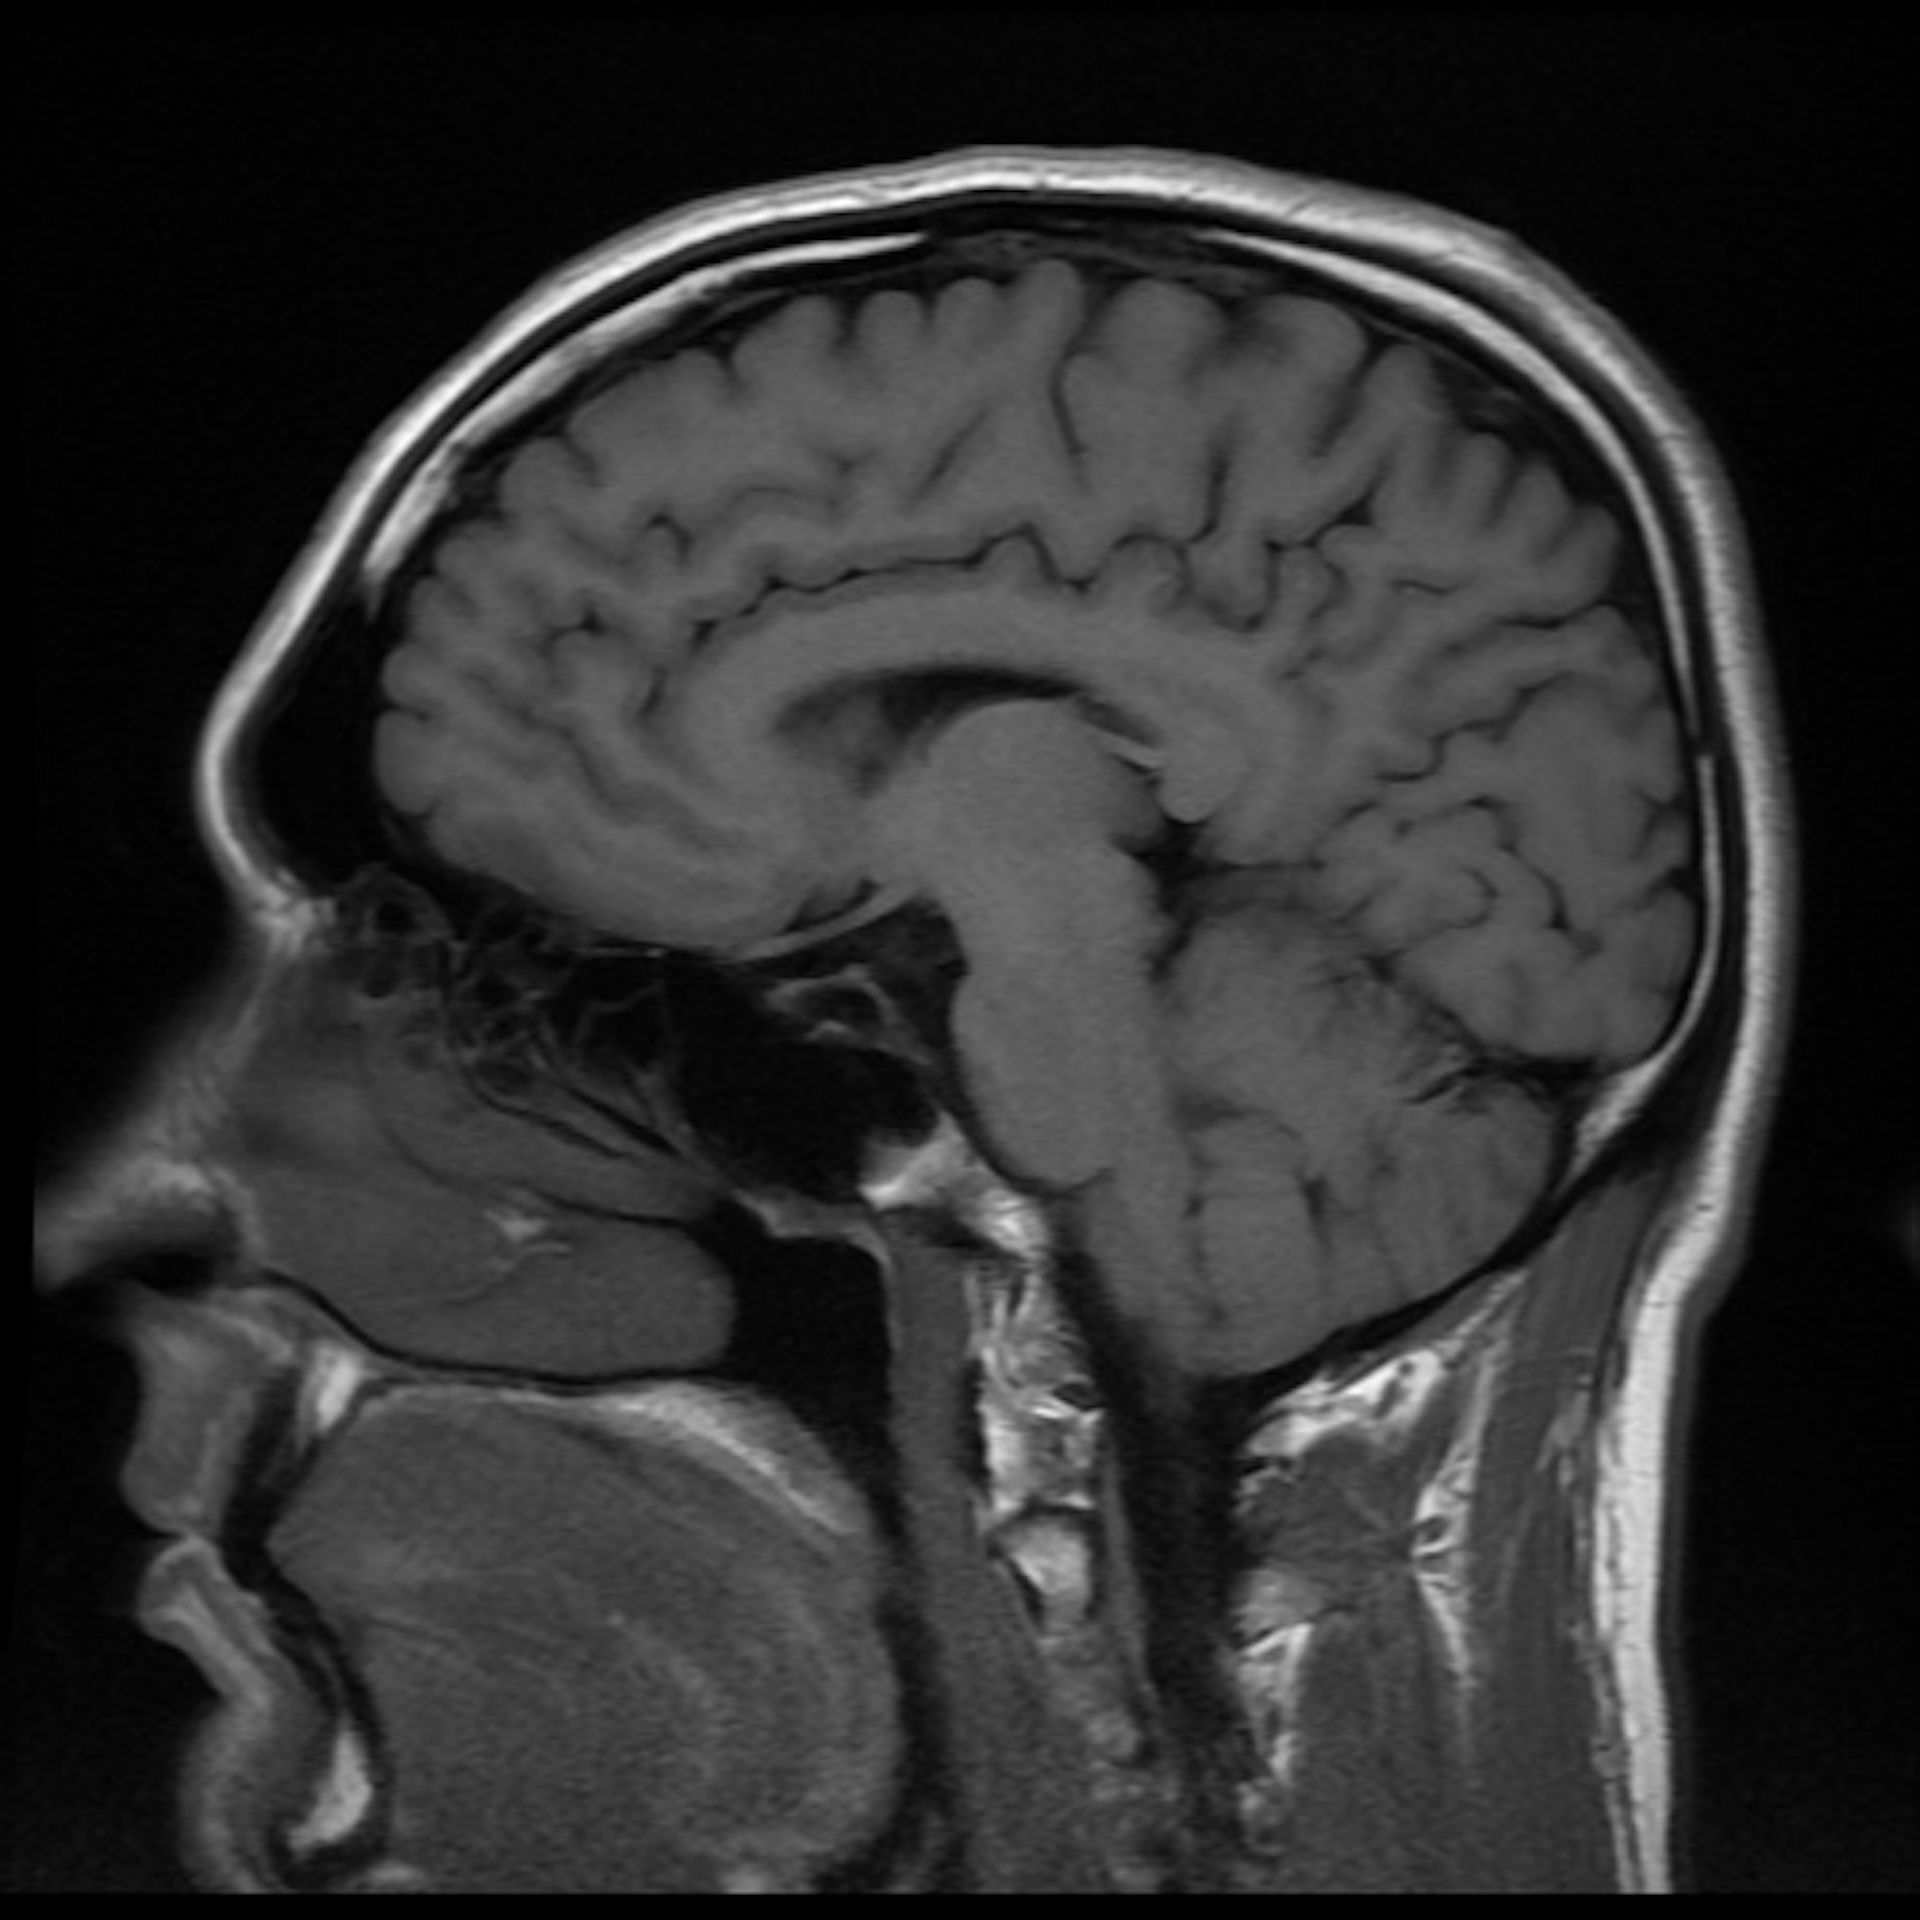

An mri uses powerful magnets, radio waves and a computer to take images of your brain. How to know what's going on inside your brain | brain scans 101. The mri scan at your scanning centre chosen during booking. These assessments raise questions about whether a brain scan can show ptsd. Here's what a ct scan of the head and brain shows and what to expect during the test.

Regrettably, the issue of mental health remains shrouded by misunderstanding and stigma. Mri is the most sensitive imaging method when it comes to examining the structure of the brain and spinal cord. Brain scans can show increased metabolism and reduced volume in the frontal lobe region of the brain in major depressive disorder. An mri uses powerful magnets, radio waves and a computer to take images of your brain. Go to a doctor immediately if you are experiencing these symptoms. For oral contrast, you will be given a liquid contrast preparation to swallow. Before the scan, you may be injected with a dye called contrast, through an a cannula which is placed into a vein in the arm. These assessments raise questions about whether a brain scan can show ptsd.